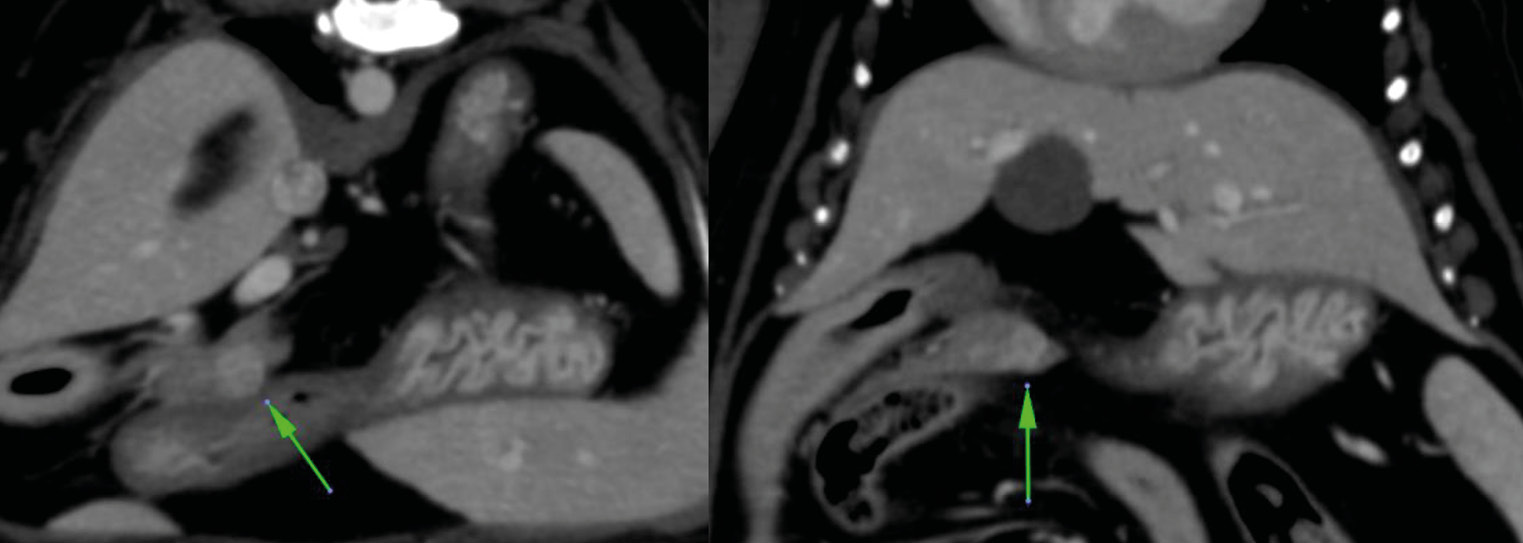

La cirugía de elección es la pancreatectomía parcial y la resección de losnódulos linfáticos (NNLL) centinelas (imágenes 3A-3I). La quimioterapia intracavitaria puede controlar la efusión por carcinomatosis secundaria, pero ofrece una respuesta paliativa de corta duración. La pancreatectomía completa o pancreaticoduodenectomía (técnica de Whipple), descritas en el perro, presentan altas tasas de morbilidad y mortalidad operatorias. La técnica de Billroth II es una opción paliativa a corto plazo en casos de obstrucción intestinal. En un estudio retrospectivo en 34 pacientes felinos con carcinoma pancreático exocrino primario la enfermedad se asoció con una historia previa de diabetes mellitus.35 El carcinoma pancreático exocrino canino se caracteriza por una alta tasa de metástasis y un pronóstico grave general.37

Imágenes 3A – 3I. Secuencia de imágenes quirúrgicas en un perro (con las imágenes del TC), durante una pancreatectomía parcial del lóbulo izquierdo y cuerpo del páncreas, usando un sellador vascular/tisular, por carcinoma pancreático.